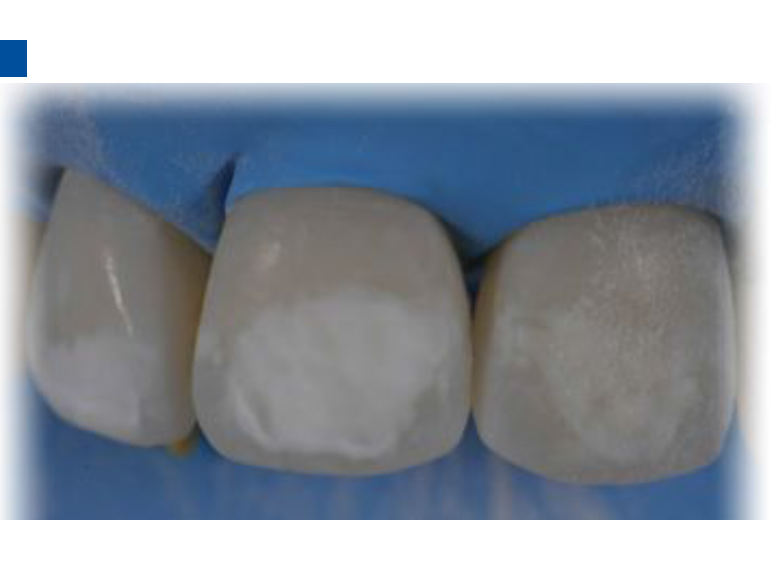

二、爱康渗透树脂唇颊面装Icon Caries Infiltrant – vestibular,治疗唇颊面釉质早期龋。(整个套装包含一次治疗两至三个早期龋损所需的材料。一次性使用,如果邻牙有类似病变可一并治疗)。

2.酸蚀后的牙釉质表面呈白垩色,如未呈现此颜色则需重复酸蚀。